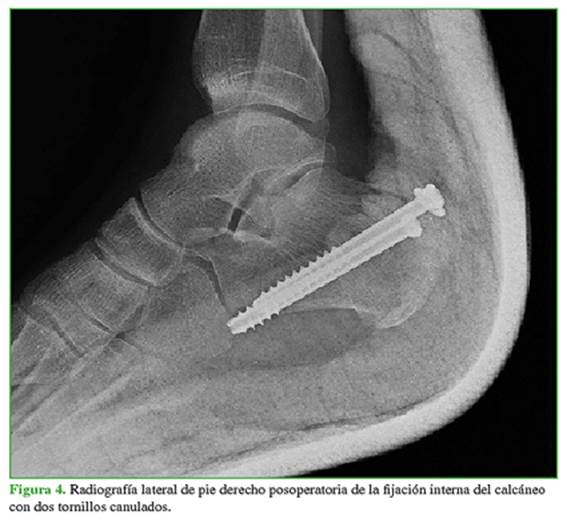

Inicialmente se le administra un tratamiento analgésico y antibiótico, y se lo inmoviliza con una férula suropédica. Se solicitan radiografías que revelan una fractura de la tuberosidad posterosuperior del calcáneo (Figura 2); luego se realiza una TC para su caracterización y se observa un desplazamiento de 1,2 cm, por lo que se indica un manejo quirúrgico (Figura 3); sin embargo, el procedimiento fue diferido debido al marcado edema de los tejidos blandos asociado a flictenas hemorrágicas; por lo tanto, en el Servicio de Urgencias, se procedió a la reducción cerrada e inmovilización con férula suropédica más flictenólisis. Al octavo día del ingreso hospitalario, se observa una marcada mejoría clínica de los tejidos blandos, por lo que no se consideró la estabilización mediante un tutor externo y el paciente es sometido a un procedimiento quirúrgico definitivo mediante reducción abierta con fijación interna del calcáneo con dos tornillos canulados de 6,5 mm, de posterior a anterior y de cefálico a caudal (Figura 4). Se opta por continuar el manejo con inmovilización mediante yeso suropédico por seis semanas. En el control posoperatorio, se retira el yeso y se inicia la recuperación mediante terapias físicas. Después de los tres meses, la evolución de la movilidad del pie derecho es favorable (Figura 5).